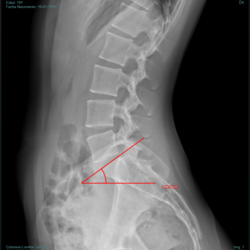

La MRH II E en versión digital, cuenta con una consola de adquisición que proporciona un programa avanzado de postprocesamiento que incluye: medición de distancias, ángulos, índice cardiotorácico, ángulo de Cobb, medición de eje mecánico, composición de huesos, textos largos , elaboración de reportes, grabación de CD con visor DICOM, entre otras herramientas.

Ángulo de Cobb

Medición Férguson